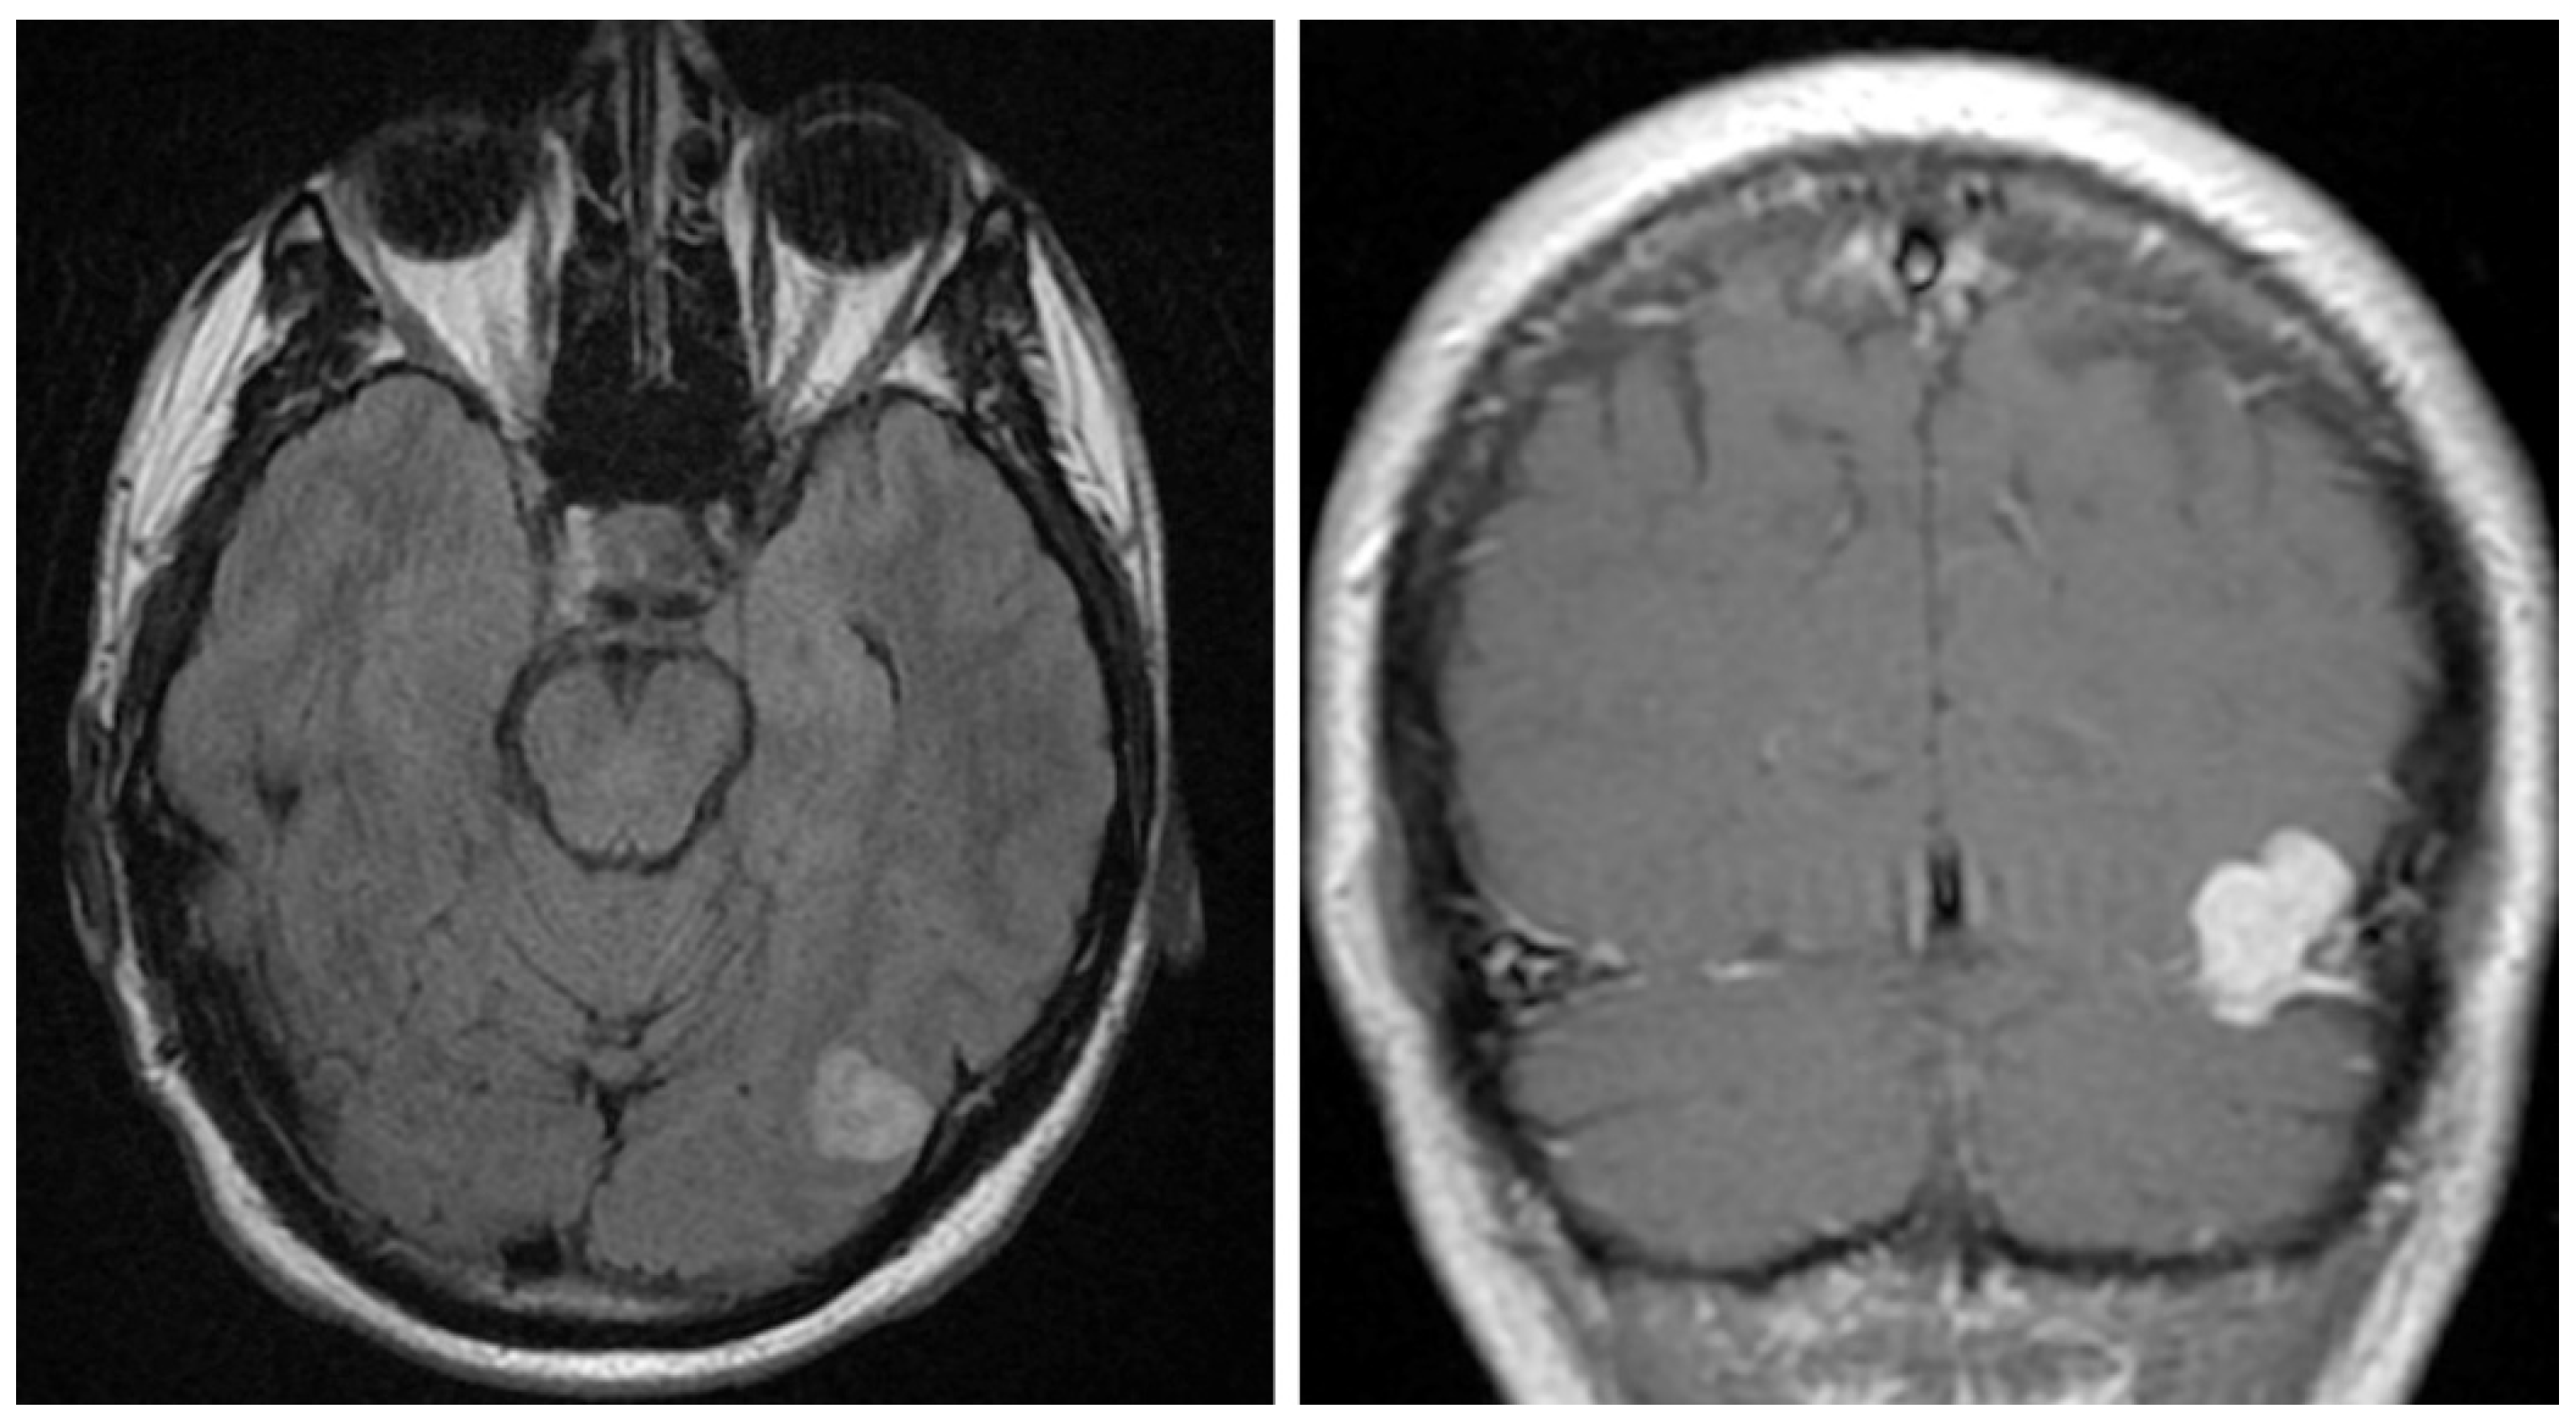

2. Case Presentation